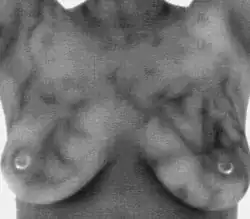

- Termografia (DITI): wykrywa różnice w emisji promieniowania podczerwonego (fale cieplne), występujące na skutek różnic w metabolizmie i unaczynieniu okolicy guza. Nadal rozwijana[196], dotychczas nie uzyskała rekomendacji FDA[197] z powodu dość niskiej czułości diagnostycznej[198][199].